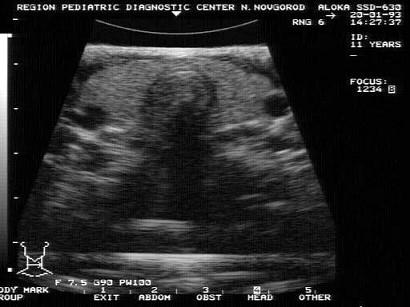

问题 结合甲状腺横断面超声声像图,甲状腺为?(?)

选项 A.均质体 B.非均质体 C.无界面区 D.强回声区 E.以上均不是

答案 A